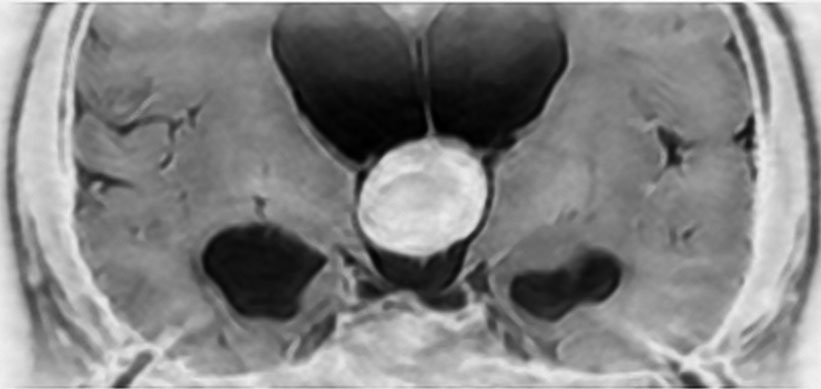

典型的な神経腸嚢胞 neurenteric cyst

左のT2強調画像で等信号,中のT2*で高信号,右はCISS画像です。

T1強調画像では,のう胞周囲の高信号の部分は半固体で,中心部の高信号はドロドロの粘液でした。基本的にガドリニウム増強はされません。まれに薄い膜状に一部が増強されることがあります。

境界明瞭は袋状の腫瘍です。椎骨動脈や脳底動脈を包み込むようにふくらんでいます。